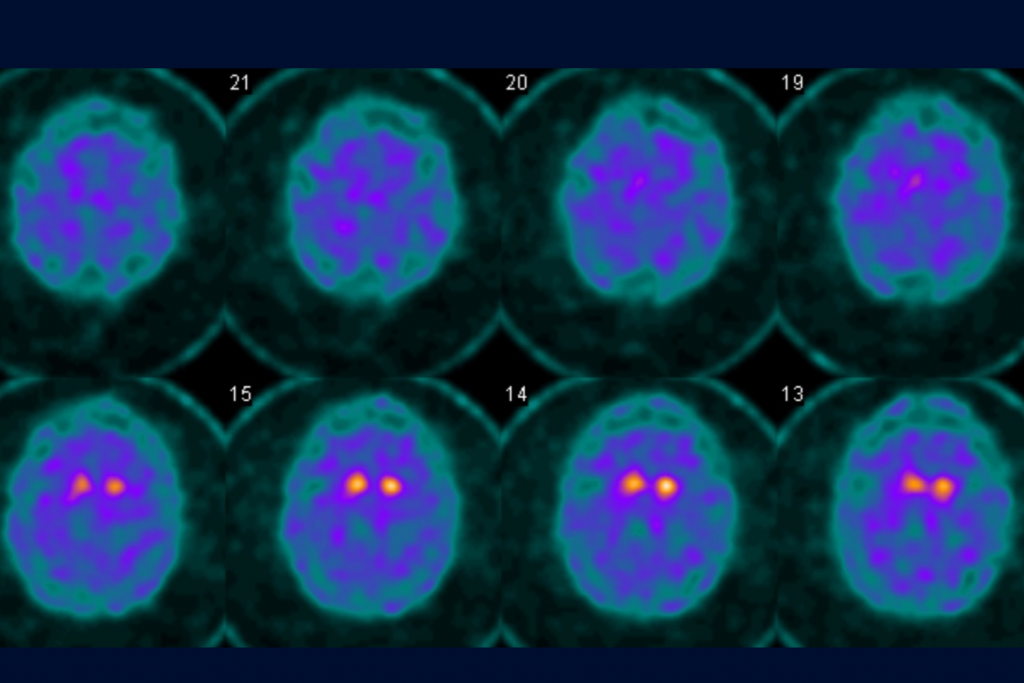

Bill is only in his fifties, but was diagnosed recently with Parkinson's disease at UConn Health's Brain and Spine Institute. The diagnosis was further supported through a DaTscan (dopamine transporter scan) using a radioactive tracer to confirm the disease's hallmark – low dopamine in the brain.